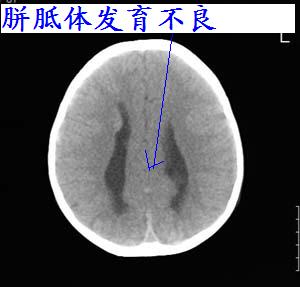

以下是引用lixi在2006-12-5 21:06:00的发言:[br]1、dandy-walker变异。2、胼胝体发育不良。

以下是引用zhuoshandiao在2006-12-5 21:41:00的发言:[br]胼胝体发育不良应该是肯定的。另外考虑dand-walker畸形。

以下是引用卜一在2006-12-5 22:30:00的发言:[br]支持考虑:1、dandy-walker变异。2、胼胝体发育不良